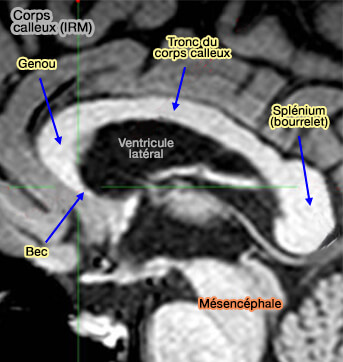

IRM du corps calleux

(Figure : vetopsy.fr d'après Slosman)

Le sillon calleux (ou du corps calleux) délimite le lobe limbique des faces médiales du lobe frontal et du lobe pariétal.

• Il s'enroule autour du corps calleux en entier, du bec (rostrum) jusqu'au bourrelet (splénium).

• Le sillon calleux sépare le corps calleux du gyrus cingulaire.

2. Le corps calleux, qui ne se trouve que chez les Mammifères placentaires, peut être subdivisé en plusieurs parties.

a. Le genou du corps calleux (Genu corporis callosus), fortement plicaturé vers le bas et vers l'arrière, devant le septum pellucidum, en constitue la partie orale.

b. Le bec (Rostrum) est la partie terminale rostrale très effilée du genou qui contacte en dessous la lame terminale et qui s'étend des foramen interventriculaires (trous de Monro) à la base du pédicule optique (loupe radiations optiques).

Ces deux parties servent d'union aux deux lobes frontaux.

c. Le tronc (Truncus) poursuit le genou vers l'arrière, et unit les deux lobes pariétaux et temporaux.

d. Le bourrelet du corps calleux (Splenium corporis callosi), " bandage " en grec, constitue la partie caudale renflée, la plus épaisse du corps calleux située au dessus de la toile choroïdienne (Tela choroidea) du 3ème ventricule et du mésencéphale : elle relie les deux lobes occipitaux.

La partie rétrécie entre le tronc et le splénium est appelée " isthme ".